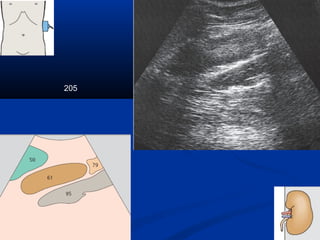

205